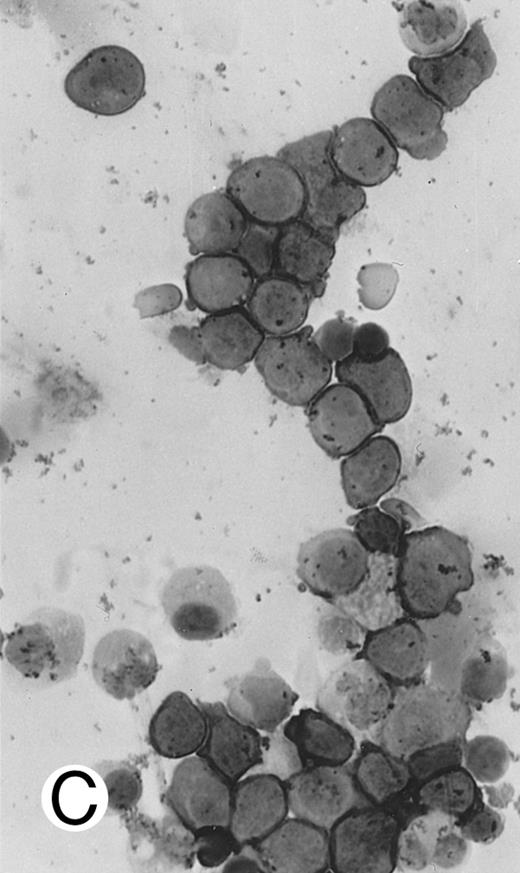

Immunocytochemical staining of aggressive NK cell leukemia/lymphoma (case no. 39), using the labeled avidin-biotin alkaline phosphatase system. The smears were prepared from mononuclear cells separated by density gradient centrifugation using Ficoll-Isopaque. (A) The cells are positive for CD2. (B) There is no reactivity for Leu4/CD3; the strongly stained small lymphocytes serve as internal positive controls. (C) The cells are reactive for CD56 (NKH1).